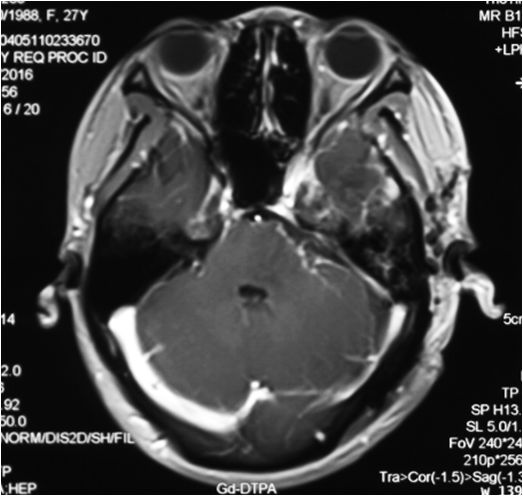

鲍遇海教授:前庭神经鞘瘤的膜及包膜的手术 意义

坐位听神经瘤切除术视频(摘自鲍教授上述讲课)

鲍遇海教授:坐位听神经瘤切除术

听神经瘤